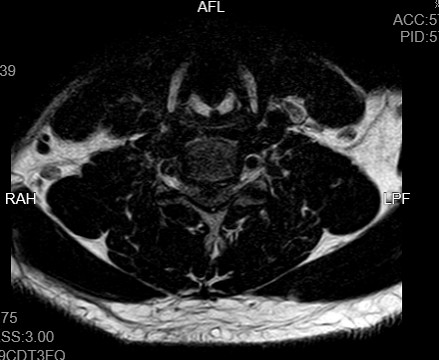

近期,年轻的阿明突然出现一侧肢体无力,开始家人以为“脑中风”,后明确原来为颈椎病椎间盘急性脱出,在广东省人民医院(下称“省人医”)帮扶下,我院骨科予以手术治疗,效果良好,手术后3天顺利出院,患者及家属对医生表示了由衷的感谢!